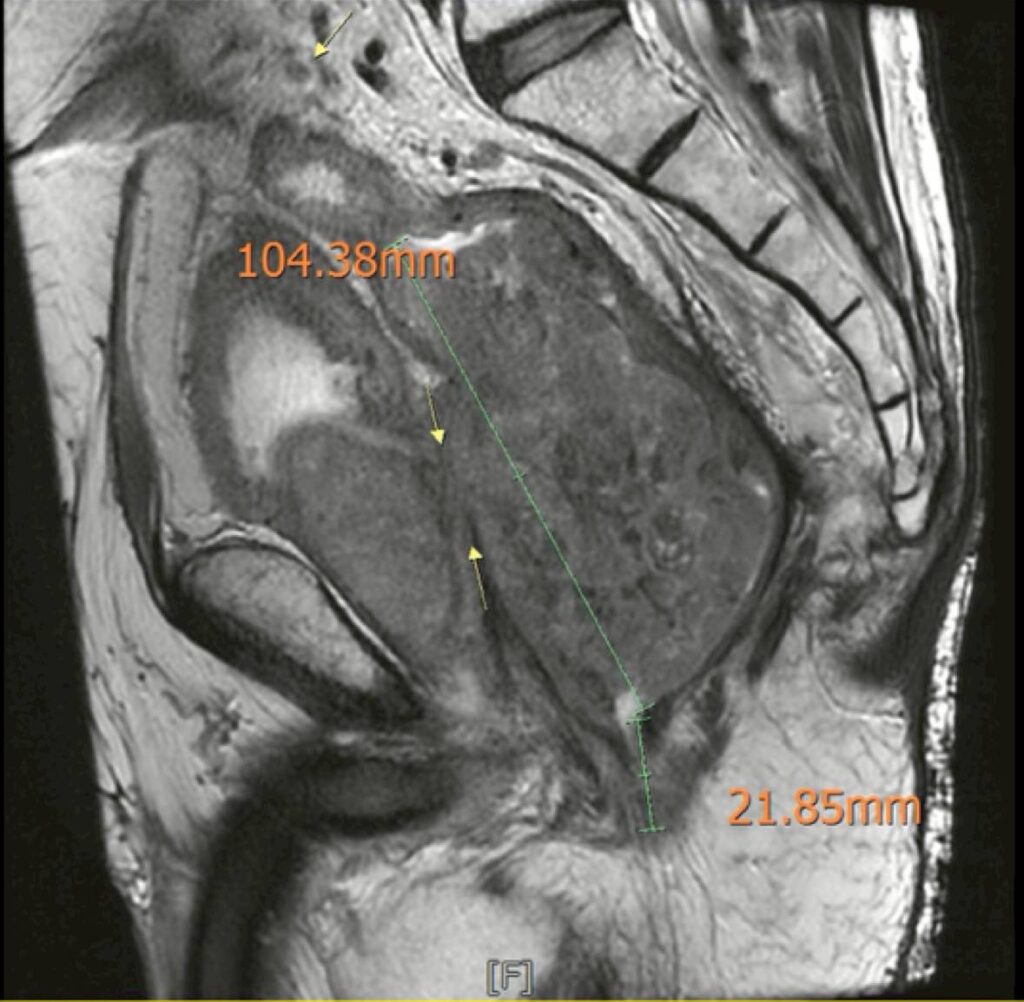

《圖說》腫瘤大小核磁共振照片。(黃晟瑋醫師提供)

在感染穩定之後,黃晟瑋醫師重新安排影像檢查,結果顯示:腫瘤處於穩定狀態,沒有遠端轉移,也沒有明顯惡化。這代表一件很重要的事情─腫瘤仍然有機會透過手術完整切除。